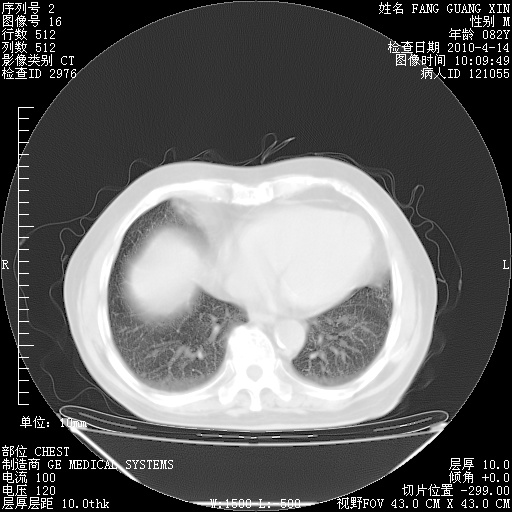

4月28日肺部CT——再次出现类似去年5月9日——透光度降低,(影像科认为)“间质性”改变。

4月28日肺部CT——再次出现类似去年5月9日——透光度降低,“间质性”改变。